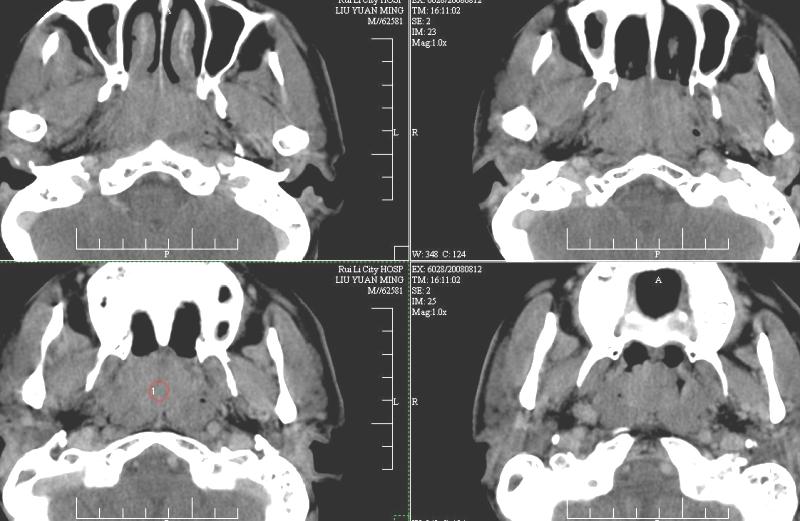

以下是引用ydx_74在2008-8-12 22:09:00的发言:[br]不考虑鼻咽癌。没有淋巴结肿大,没有颅底骨质破坏,咽隐窝、咽鼓管咽口存在,咽旁间隙清楚,平扫ct值34hu,增强动脉期81hu,实质期约85hu,增强幅度达50多,除外增强时机没有掌握好因素,可以考虑鼻咽纤维血管瘤吗?

以下是引用卜一在2008-8-13 8:07:00的发言:[br][br] 鼻咽部新生物,性质待定(不排除鼻咽癌可能);建议行鼻咽镜检查(活检)。 [br]支持!